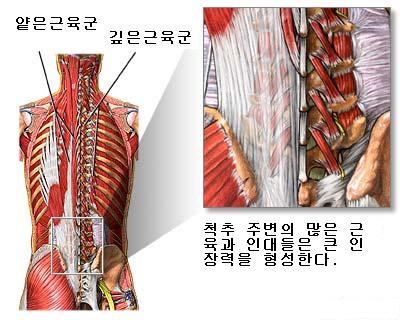

허리를 잡아주는 즉, 척주를 정상적인 S자로 유지할 수 있도록 해주는 근육들이 있는데, 주로 복근, 배부신근, 대둔근(엉덩이 근육)과 슬괵근(뒷허벅지 근육), 고관절 굴곡근 등을 주축으로 이루어 진다. 신경은 뇌와 인체 각 기관을 연결하여 모든 근육, 관절, 뼈를 조절하고, 오장육부의 기능과 전신의 생리기능을 주관한다. 따라서 신경의 압박은 곧 많은 질병을 유발시키는 주요한 인자이다. 평소 자세가 불량하다던지 외상을 입거나 오장육부의 질환으로 척추의 균형이 깨지면 많은 질병이 생기게 되는 것이다.